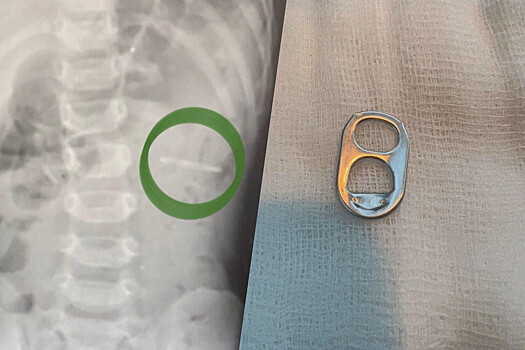

Врачи Раменской больницы спасли полуторагодовалого ребенка, который проглотил ключ от металлической банки. Об этом сообщили в пресс-службе минздрава Московской области.

Мальчика в больницу привезли родители. Они рассказали, что сын играл с маленькой деталью и по неосторожности проглотил ее. Обследование показало, что ключ от банки находится в желудке.

«Слизистые оболочки внутренних органов были не повреждены. При помощи эндоскопического инструмента металлический предмет с острыми краями был аккуратно извлечен», — рассказал заведующий детским хирургическим отделением больницы Владимир Хабалов.